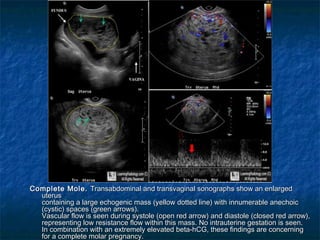

Complete Mole.Complete Mole. Transabdominal and transvaginal sonographs show an enlargedTransabdominal and transvaginal sonographs show an enlarged

uterusuterus

containing a large echogenic mass (yellow dotted line) with innumerable anechoiccontaining a large echogenic mass (yellow dotted line) with innumerable anechoic

(cystic) spaces (green arrows).  (cystic) spaces (green arrows).

Vascular flow is seen during systole (open red arrow) and diastole (closed red arrow),Vascular flow is seen during systole (open red arrow) and diastole (closed red arrow),

representing low resistance flow within this mass. No intrauterine gestation is seen.representing low resistance flow within this mass. No intrauterine gestation is seen.

In combination with an extremely elevated beta-hCG, these findings are concerningIn combination with an extremely elevated beta-hCG, these findings are concerning

for a complete molar pregnancy.for a complete molar pregnancy.

Complete Mole.Complete Mole.Transabdominal and transvaginal sonographs show an enlargedTransabdominal and transvaginal sonographs show an enlarged uterusuterus containing a large echogenic mass (yellow dotted line) with innumerable anechoiccontaining a large echogenic mass (yellow dotted line) with innumerable anechoic (cystic) spaces (green arrows).  (cystic) spaces (green arrows).   Vascular flow is seen during systole (open red arrow) and diastole (closed red arrow),Vascular flow is seen during systole (open red arrow) and diastole (closed red arrow), representing low resistance flow within this mass. No intrauterine gestation is seen.representing low resistance flow within this mass. No intrauterine gestation is seen. In combination with an extremely elevated beta-hCG, these findings are concerningIn combination with an extremely elevated beta-hCG, these findings are concerning for a complete molar pregnancy.for a complete molar pregnancy.